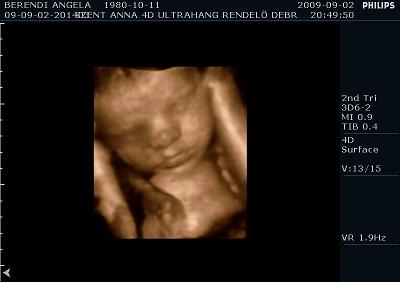

Ma voltunk UH-on. És a méretei alapján még mindig egy héttel idősebbnek nézik, de súlya tök normális 2350 gramm. Szóval azt mondják nem lesz akkora mint a kis Levi manó volt. Ennek azért örülök mert nagyobb az esély hogy meg tudom szülni, mivel nekem az első császár volt. Szóval drukkoljatok lányok!!